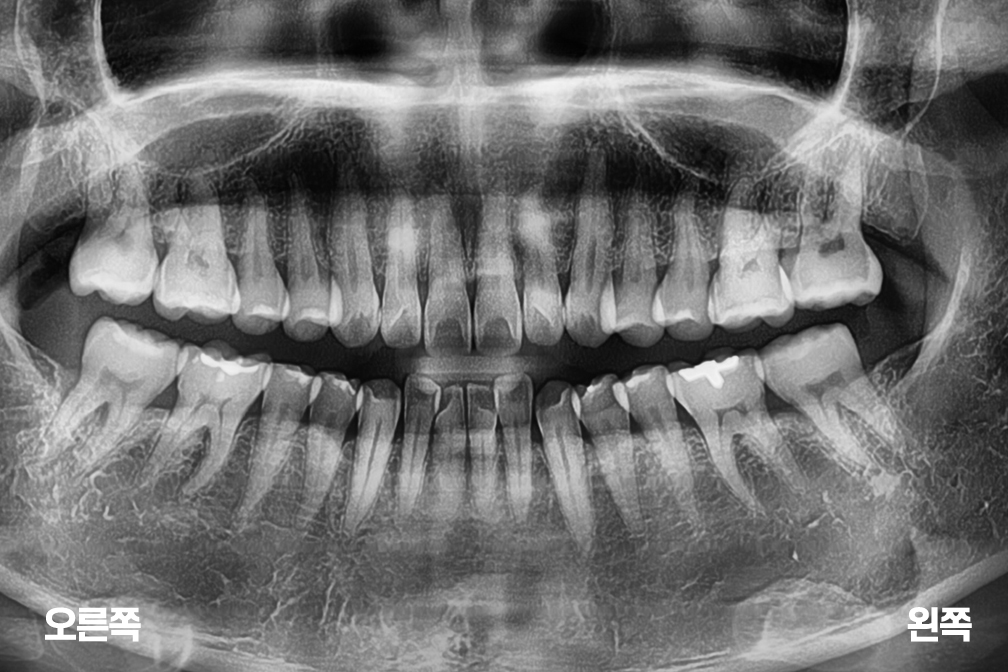

임플란트 오른쪽 아래 어금니 임플란트

After 2026년 3월 6일